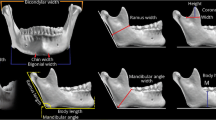

The magnification of linear measurements from each cephalogram used in this study was 10%. Nineteen cephalometric landmarks in each radiograph were identified and digitized (Fig. 1). We chose the sella to nasion (SN) line, the Frankfurt horizontal (FH) plane, and the basion to nasion (BaN) line as reference lines or planes, commonly used in lateral radiographic cephalometric analyses. Calculations of 22 cephalometric measurements (Table 2) were performed using a computerized cephalometric system, Winceph (version 8.0, Rise Co., Japan). Cephalometric data were analyzed using the SAS program (version 9.1; SAS Institute Inc., Cary, NC, USA). Descriptive statistics, including means, standard deviations, and Student’s t test, were obtained for each of the measurements (Table 3).

Cephalometric landmarks. 1 Nasion, 2 glabella, 3 V1 (upper parameter of frontal sinus cavity), 4 V2 (lower parameter of frontal sinus cavity), 5 H1 (anterior parameter of the frontal sinus cavity on inner bregma to nasion line), 6 H2 (posterior parameter of the frontal sinus cavity on inner bregma to nasion line), 7 supraglabella, 8 metopion, 9 bregma, 10 opisthocranion, 11 inion, 12 opisthion, 13 mastoidale, 14 B2 (posterior parameter of the mastoid width at the level of cranial base), 15 B1 (anterior parameter of the mastoid width at the level of cranial base), 16 basion, 17 porion, 18 orbitale, 19 sella